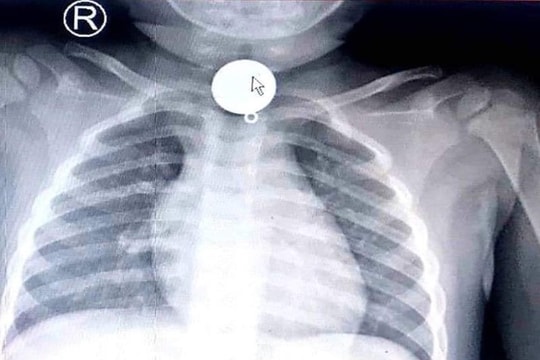

Bé trai 2 tuổi tắc ống thực quản vì nuốt mặt dây chuyền

Trong lúc chơi đùa, bé trai 2 tuổi đã nuốt phải mặt dây chuyền làm chắn ngang nắp thực quản.